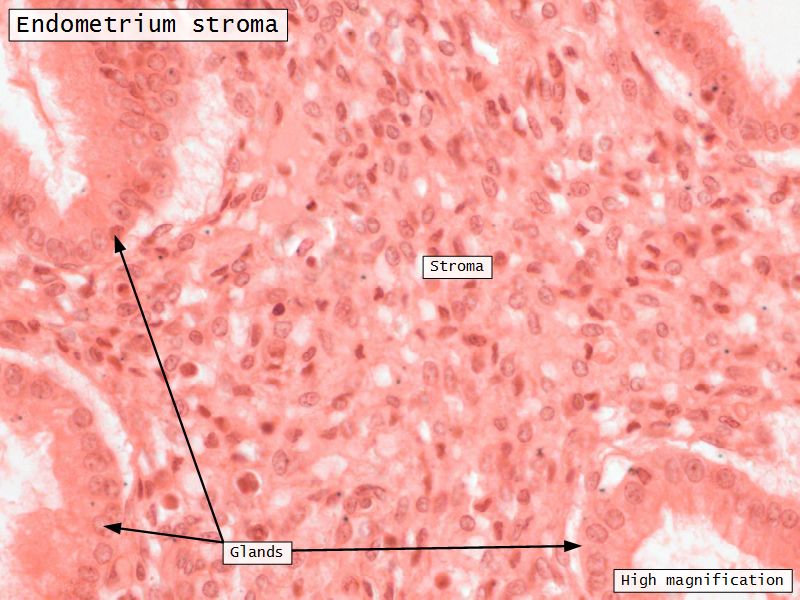

Endometrium Stroma

- Mesenchymal-like CT

- Reticular fibres

- Stellate-shaped cells

- Macrophages

- Lymphoid elements

- Functional layer

- Basal layer

Functional layer

- Thick superficial layer

- Cyclic monthly hormonal changes

Basal layer

- Thin deeper layer

- Preserved during menstruation